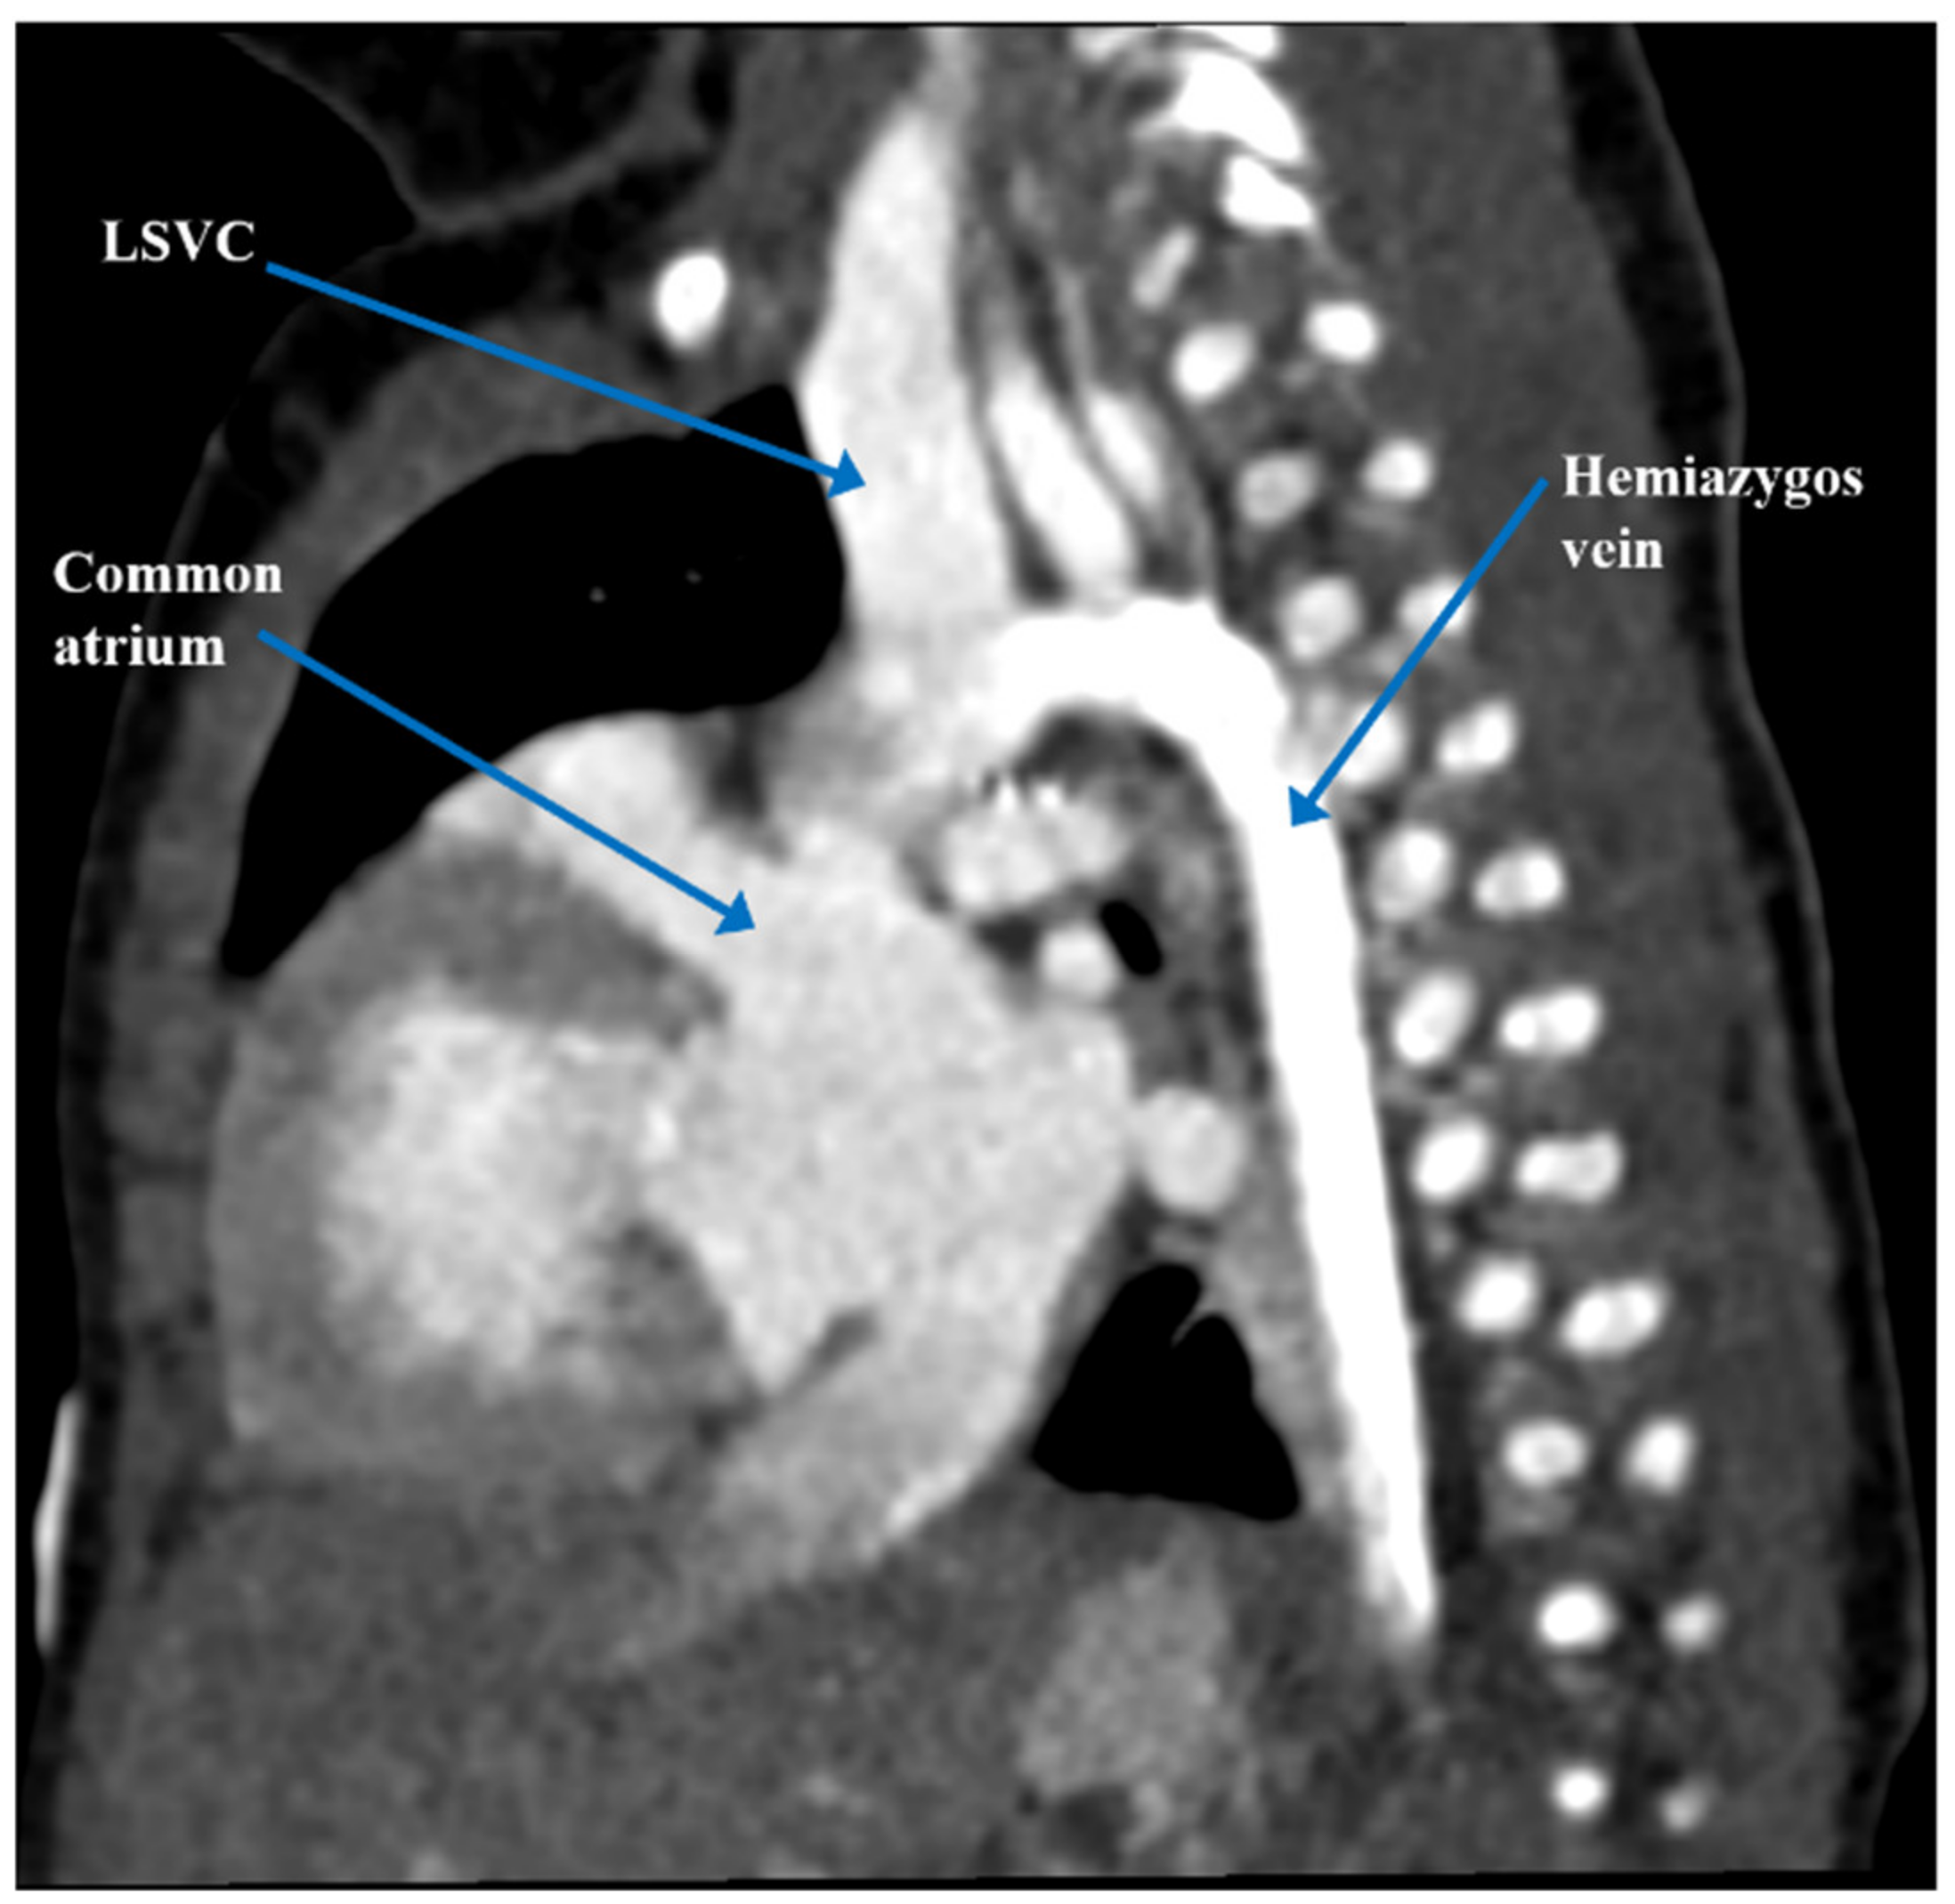

| Present case [6] | Heterotaxy syndrome with partial LPA sling, partial AV canal with a common atrium, atrial situs ambiguous, interrupted IVC, VSD, and PDA | 5 months | PDA occlusion, clipping and division of the anomalous LPA | Defined complex anatomy and surgical plan for biventricular repair | Biventricular repair |